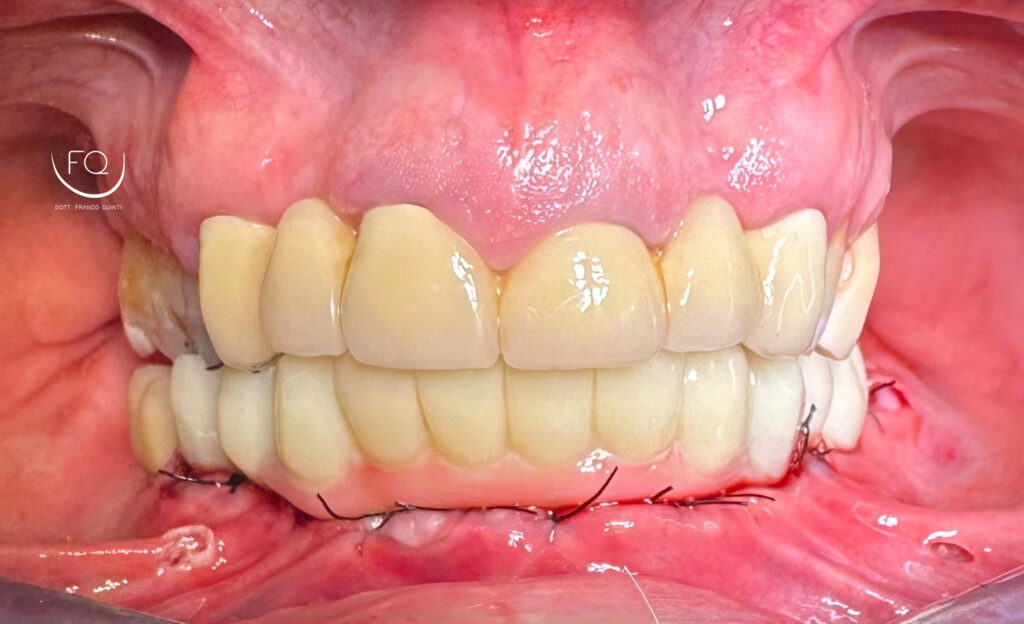

Dall’immagine iniziale è possibile apprezzare l’estrusione del gruppo incisivo inferiore il quale è stato corretta con la protesi provvisoria a carico immediato stampata in 3D.